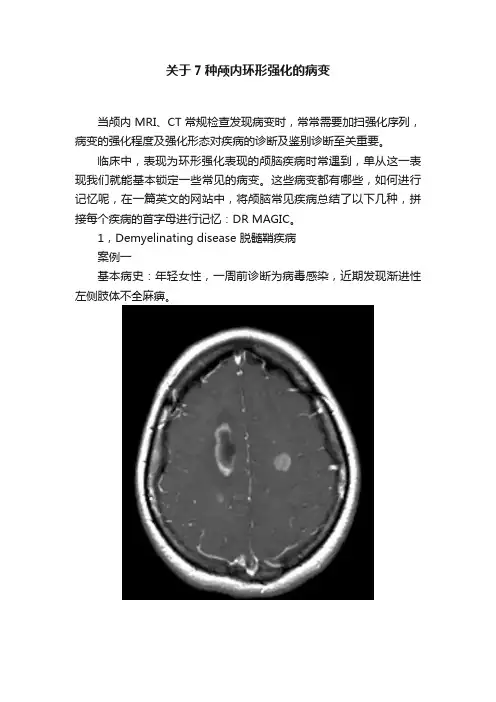

1,Demyelinating disease 脱髓鞘疾病案例一基本病史:年轻女性,一周前诊断为病毒感染,近期发现渐进性左侧肢体不全麻痹。

图 1 颅脑强化MRI轴位和冠状位图像显示双侧放射冠区多发异常强化,右侧较大病灶呈环形强化表现,最终病变证实为急性播散性脑脊髓炎2,Radiation necrosis 或者Resolving haematoma 放射性坏死或者溶解期血肿案例二基本病史:腺癌颅内转移患者,行放射性治疗后复查MRI如下。